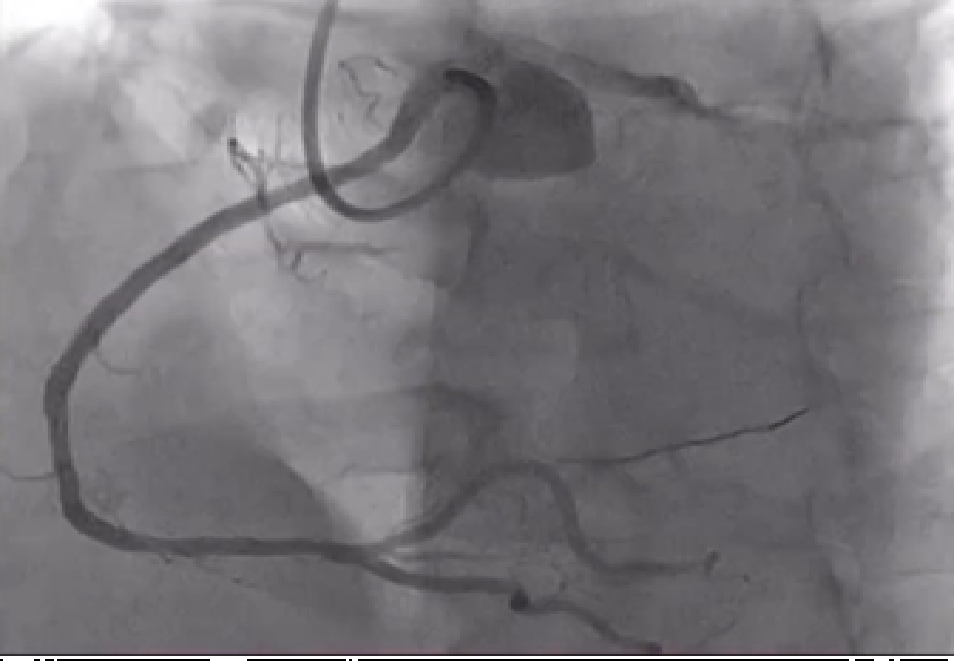

MOVIE-0013.mp4

Diagnostic angiography has been performed and occluded Left Anterior descending artery was visualized but, the right coronary artery couldn't be find from the right coronary ostium. 6F EBU 3.5 catheter trough the right radial approach has been inserted and we could visualize right coronary artery arising from the left coronary ostia. Direct stenting was performed with 3.5/38mm DES at 17 atm. After this procedure we continued to LAD, passed the occlusion with BMW wire after which predilatation with 2.5/20 mmx 14 atm has been performed and after that 3.0/28mm DES at 15atm was implanted with good end result